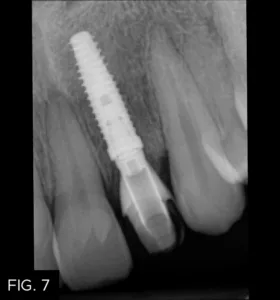

The healing time for the temporary crown was six months, during which time the patient was instructed to wear his aligners nightly. Once tissue healing was achieved (FIG. 6), the temporary crown was removed, and an implant transfer was placed and verified with a periapical radiograph. (FIG. 7)

A final impression was taken with polyvinyl siloxane impression material (Affinity, Clinician’s Choice). The final shade selection, multiple photographs for the technician, and a bite registration were also obtained at this time. (FIG. 8) The temporary crown was then re-cemented. An impression of the temporary crown was also sent to the laboratory to communicate the emergence profile to be replicated.